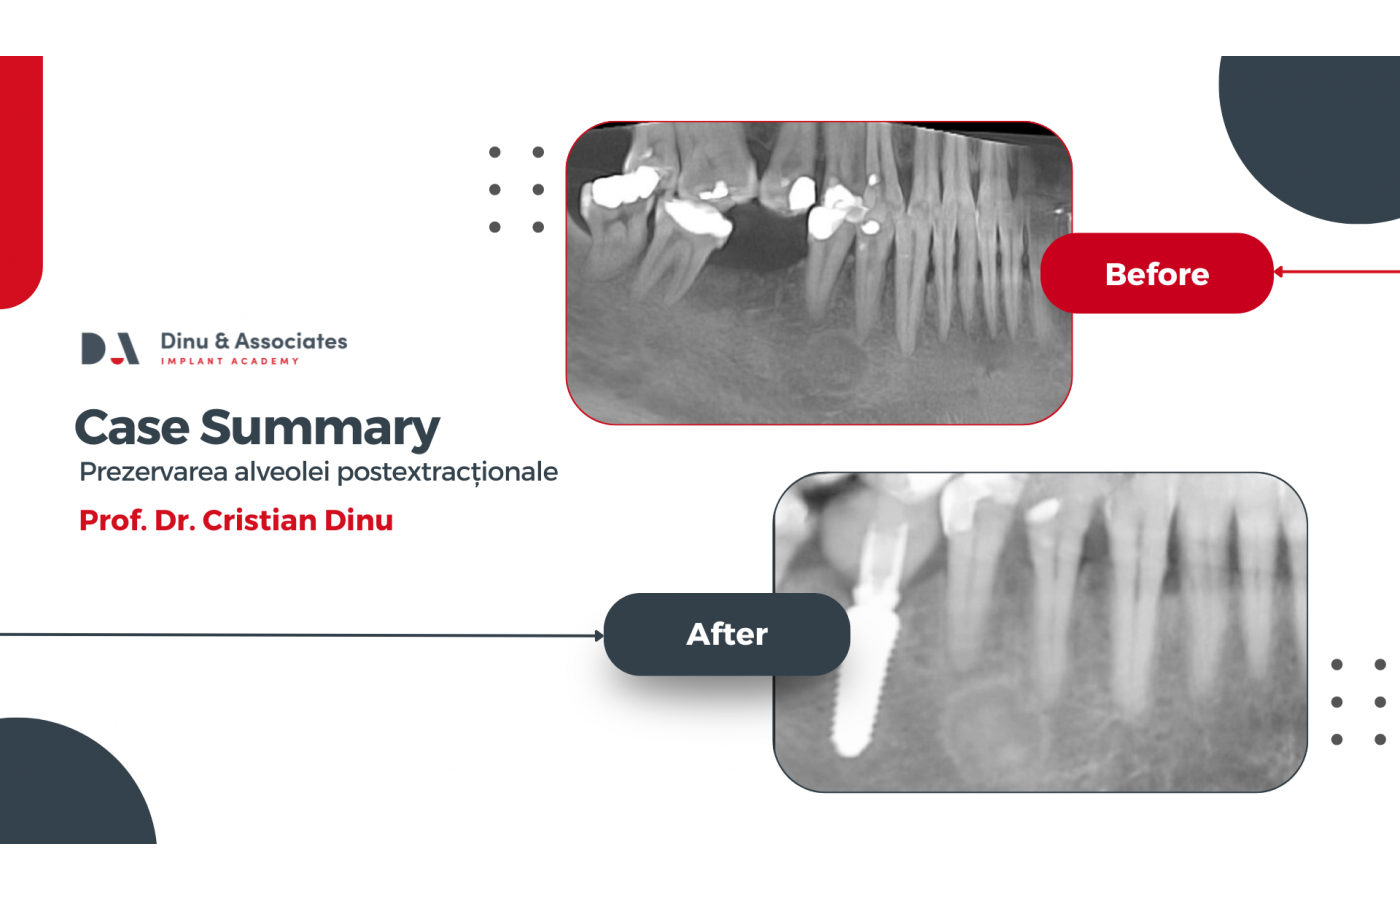

Studiu de caz și video: Prezervarea alveolei postextrationale. Intervenție realizată de prof. dr. Cristian Dinu

Pacienta, în vârstă de 67 de ani, s-a prezentat pentru evaluarea dintelui 4.6, pentru care tratamentul endodontic efectuat în antecedente nu a avut succes. În urma examinării imagistice și clinice multidisciplinare, dintele a fost considerat compromis din punct de vedere endodontic și parodontal, fiind indicat tratamentul radical.

Prima etapă terapeutică a constat în extracția atraumatică a molarului 4.6 cu separare radiculară, chiuretajul alveolei postextracționale, planarea radiculară și tratamentul suprafeței expuse a rădăcinii dintelui adiacent, urmate de reconstrucția alveolei postextracționale.

Reabilitarea implantară a fost realizată într-o etapă ulterioară, după evaluarea imagistică a vindecării și integrării grefei osoase, care au oferit condiții ideale pentru inserarea unui implant dentar pe poziția molarului 4.6. Implantul a fost încărcat imediat fiind realizată o coroană provizorie care ulterior va fi inlocuită de lucrarea protetică definitivă.